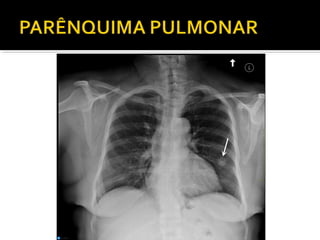

Este documento fornece parâmetros técnicos para realizar uma radiografia de tórax, incluindo posicionamento correto do paciente, dose adequada de radiação e estruturas anatômicas a serem avaliadas, como coração, pulmões, pleura, diafragma e ossos do tórax.